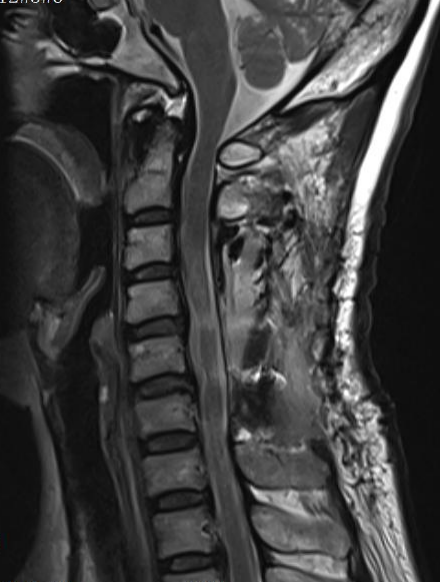

手術(shù)由程俊杰主任醫(yī)師主刀,在麻醉科和手術(shù)室的通力配合下,專家團(tuán)隊(duì)運(yùn)用超聲骨刀進(jìn)行了精準(zhǔn)截骨減壓。術(shù)中有效擴(kuò)大了狹窄的椎管,為受損的脊髓神經(jīng)創(chuàng)造了寶貴的復(fù)蘇空間。隨后,團(tuán)隊(duì)順利置入側(cè)塊螺釘內(nèi)固定系統(tǒng),位置精準(zhǔn)、固定牢靠,并進(jìn)行了關(guān)節(jié)突關(guān)節(jié)植骨融合。

術(shù)后MRI